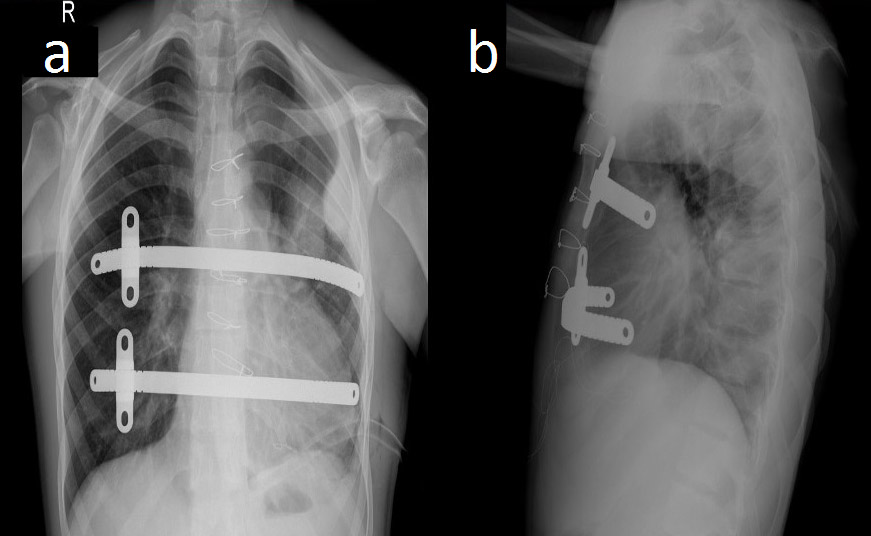

Figure 2. Postoperative chest radiographs showing the bar positions in anteroposterior (a) and lateral (b) projections.

The authors decided to perform synchronous ASD closure and correction of the pectus excavatum deformity. The patient was placed in the supine position with the arms abducted to expose the anterior and lateral chest wall. The deepest point and the bilateral highest points (thoracic entry and exit points) of the thorax were marked. Two bars were used to correct the deformity. In total, four skin incisions were made: in the third intercostal space on the left side, in the fourth intercostal space in the anterior axillary line, in the third intercostal space on the right side, and the fourth intercostal space in the anterior axillary line on the right side. Subcutaneous pockets (two left and two right) were made by blunt dissection, and a median sternotomy was performed. The introducer was slowly advanced across the anterior mediastinal space immediately under the sternotomy. Using the introducer, a strand of cloth tape was pulled through the tunnel. The tape functioned as a guide for placement of the pectus bars, and then the pericardium was opened. The patient was put on cardiopulmonary bypass, the superior and inferior vena cavae were clamped, and the aorta was clamped. Cardioplegia was administered. The ASD was closed with a pericardial patch and cardiopulmonary bypass was terminated. Sternal wires were placed for sternal closure, but were not twisted. The introducers were linked to the tape and two bars were inserted with the convexity facing posteriorly, and the sternal wires were twisted. A bar flipper was used to turn the two bars over while pulling up the sternum. The rotated bars were fixed with butterfly stabilization on the right sides of the chest, and were fixed with PDS sutures on the left side (Figure 2). There was no need to use a thoracoscope, because the authors were able to see the procedure under direct vision through the sternotomy. The incisions were closed and the patient was taken to the cardiac intensive care unit with a mediastinal and two thoracic (left and right) chest tubes.